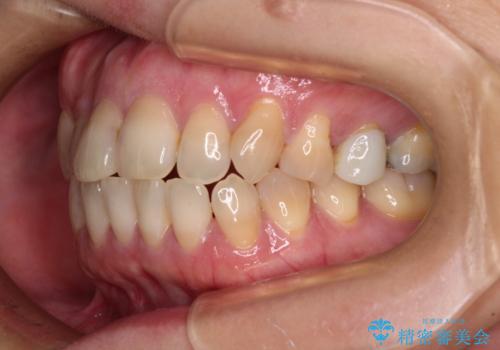

- 前歯のデコボコと口元の突出感を気にして来院された患者様です。

上下前歯がくちばしのように突出していたため、上下左右の第一小臼歯4本を抜歯し、ワイヤー装置にて矯正治療を行うこととしました。

上顎骨に対して下顎骨がやや前方位に位置しているため、歯肉退縮を回避するために下顎前歯をあまり内側に移動させることができない状況でしたが、十分に口元の突出感を改善することができました。